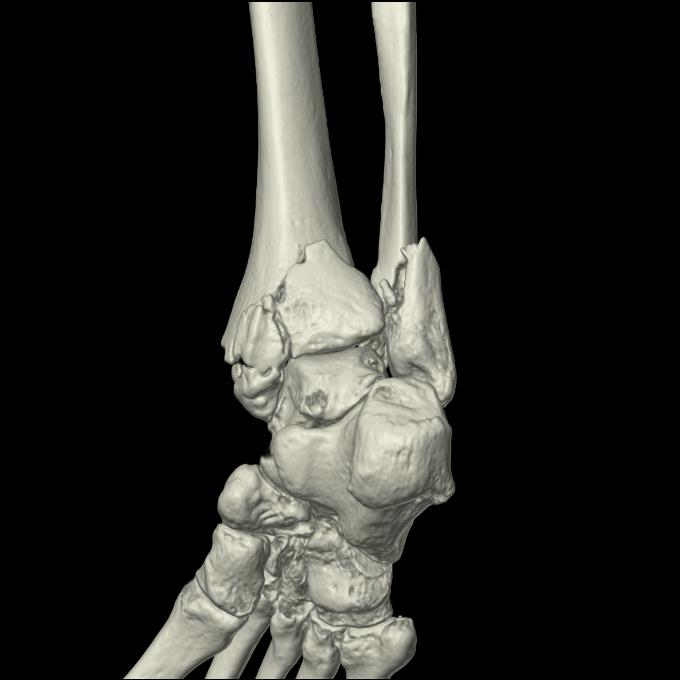

102755 1/4 2R 1/15 2R 右足関節 68歳女性 右三果脱臼骨折